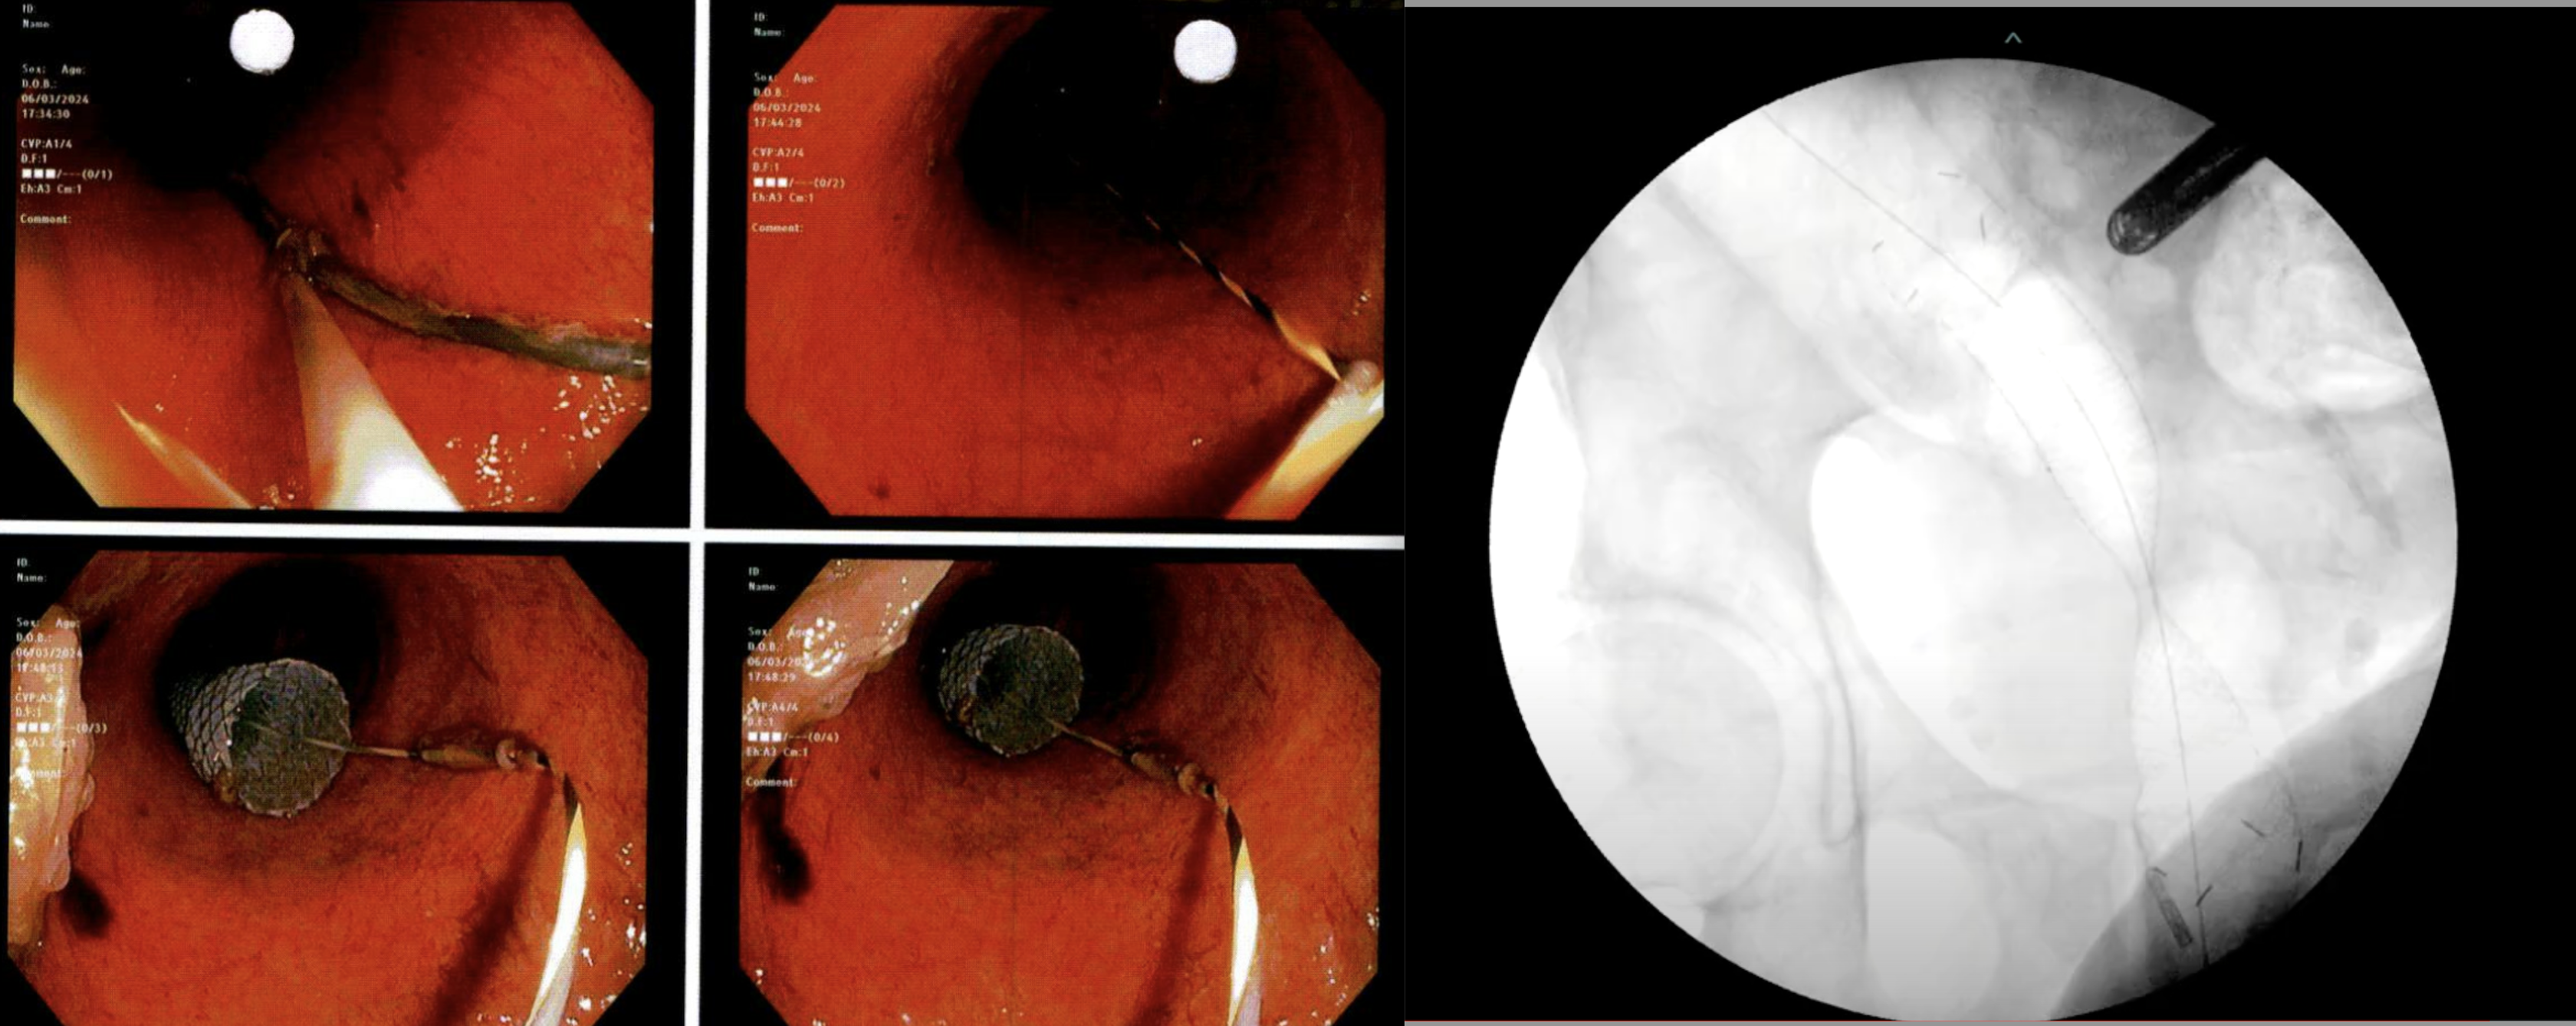

Stent guided by wire which was fed through anus via fluoroscopy; visualized with colonoscope from above (via stoma). (Left) Scope visualizing wire and stent. (Right) Fluoroscopy demonstrating wire and Stent within the sigmoid colon, and colonoscope tip proximal in the stoma.